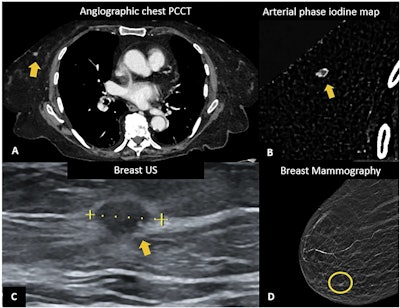

PCCT in breast cancer. Chest PCCT of a 55-year-old woman suffering from dyspnea: A angiographic chest examination showing an incidental finding of a mammary nodule in the lower inner quadrant of the right breast, with a diameter of 8 mm, with rim enhancement at arterial-phase iodine map (B). For the suspicious enhancement pattern, breast ultrasound and mammography were suggested. On the same side, breast mammography shows a small speculated margin opacity containing rare microcalcifications (D), and ultrasound (C) found a solid, hypoechoic nodule with ill-defined margins, suspected for neoplasia. Ultrasound-guided core needle biopsy was performed. At histological examination, it resulted in an invasive breast carcinoma of no special type.Bruno, Palmisano et al; Insights into Imaging